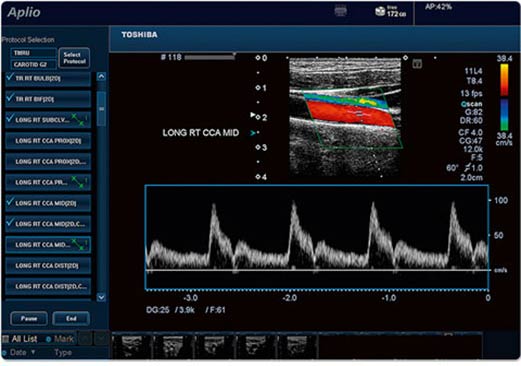

- Автоизмерение толщины стенки интима-медия,

- Регистрация высоких скоростей кровотока,

- Допплеровская визуализация тканей,

- Ускоренная параллельная обработка изображений,